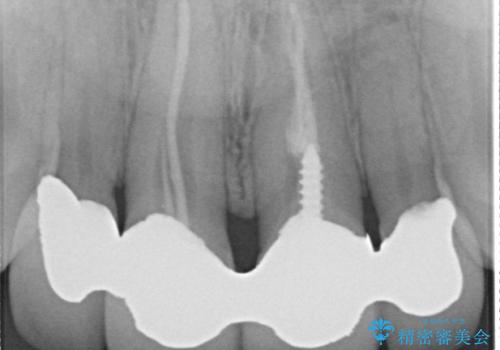

- 昔装着した前歯のかぶせ物を新しくしたいとのことで来院されました。

ご自身の歯とかぶせ物の境目が露出しておりました。

前歯の合計6本をオールセラミッククラウンにする計画としました。